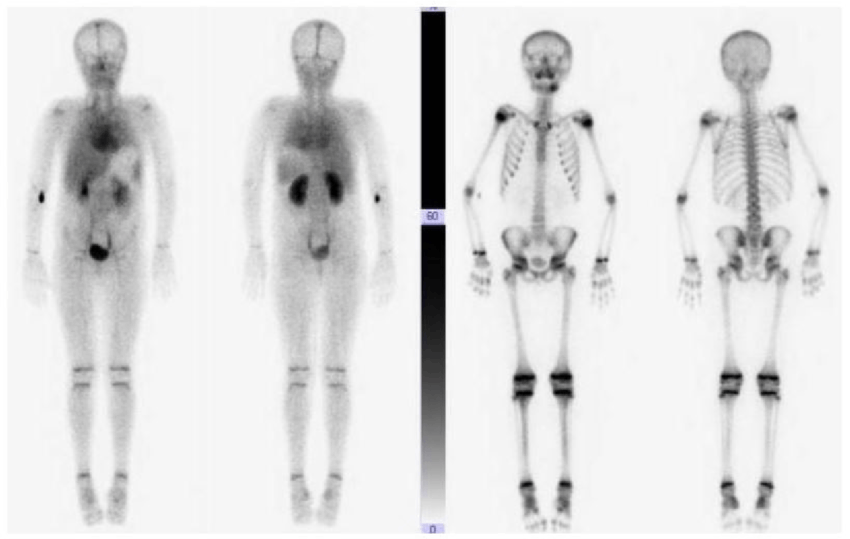

Kemik Sintigrafisi

Kemik sintigrafisi, tümörün aktivitesi ve uzak tutulum (metastaz) konusunda yardımcı olur.

PET (Positron emission tomography)

PET, glikoz metabolik aktiviteyi gösterir. Yalnız kemikte değil vücudun herhangi bir yerindeki aktivite artışınıda gösterir. Aktivite artışı tümöre spesifik olmayıp, travma iyileşmesinde ve enfeksiyonda da görülebilir.